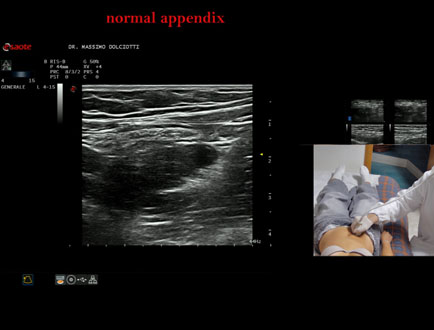

Data inserimento: 26/09/2025

Ecografia del: 12/09/2025

Strumento: Esaote MyLab Eight

Sonda: Lineare Multifrequenza 4-15 MHz

Età Paziente: F 24 anni

Motivazione dell'esame: da 3 mesi dolore al fianco destro.

Commento all'esame: le immagini ed il video documentano l'appendice di spessore normale (5,1-5,7 mm - v.n. < 6 mm).

Conclusioni: appendice normale (normal appendix).

Presentazione: Dr. Massimo Dolciotti - Ancona

Elaborazione digitale: Andrea Dini - Ancona